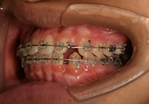

| 治療中 |

![]() ![]() ![]() |

![]() ![]() |

![]() ![]() ![]() ![]() ![]() |